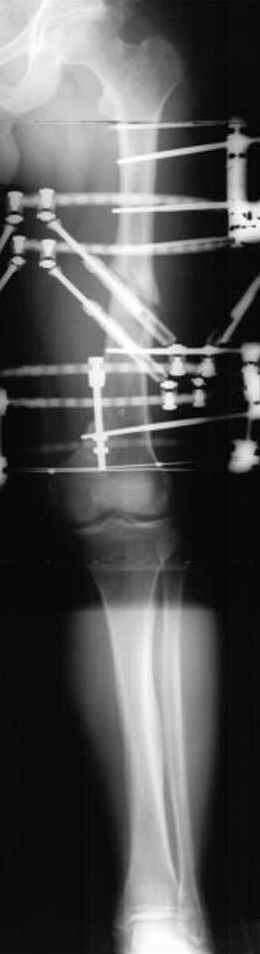

Djoldas Kuldjanov 23 Ноябрь 2004, 18:21

пластическая модель; и коррекция бедра аппаратом Илизарова.

хотя даже если бы и инфекция , то nail exchange с рассверливанием канала - вариант дебрайдмента) Я думаю, что последовательность развития событий:

Узкий к-м канал - тонкий гвоздь- усталостный перелом дистальных винтов - развитие нестабильности и как ее результат остеолиз вокруг гвоздя - деформация анатомической оси бедра. Похоже, что я понял почему аппарат, а не новый гвоздь:-)